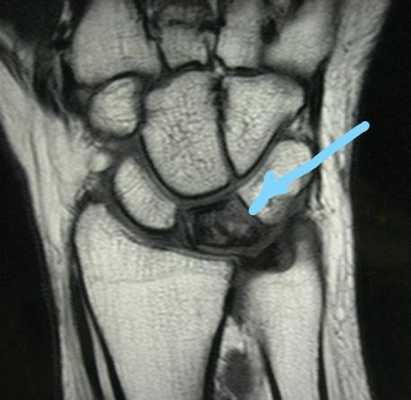

- МРТ: Объявлена лучшей методикой визуализации для Кинбека. Она чрезвычайно чувствительна и специфична для выявления остеонекроза [8]. МРТ наиболее важна на ранних стадиях заболевания (особенно на I стадии, когда простые рентгенограммы показывают норму) [7][9].

В сомнительных случаях, когда рентгенография не позволяет с уверенностью говорить о диагнозе, выполняется КТ или МРТ:

МРТ при болезни Кинбека.

Рентгенологическая визуализация, такая как МРТ и компьютерная томография, в случае болезни Кинбека, как правило, является единственным способом поставить правильный диагноз [6].

Болезнь Кинбека - это клинический и визуализирующий диагноз. Как рентгенография/компьютерная томография, так и магнитно-резонансная томография (МРТ) являются высокоспецифичными. Однако МРТ является наиболее чувствительной и выявляет рентгенологически скрытые случаи.

- КТ и МРТ лучезапястного сустава. Назначаются в сомнительных случаях на ранней стадии для выявления изменений, не отображающихся на обычных рентгенограммах.